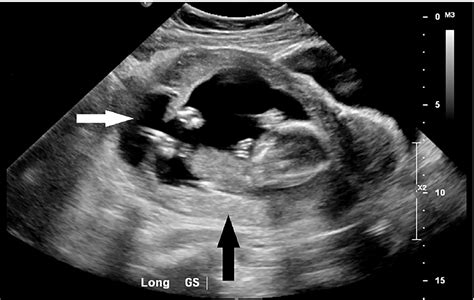

When a physician suspects an ectopic pregnancy, they often perform a transvaginal ultrasound. This procedure uses a specialized wand to provide a high-resolution view of the reproductive organs. By visualizing the uterus, ovaries, and the surrounding areas, radiologists and OB/GYNs look for specific clinical markers.

When doctors look for an ectopic pregnancy by ultrasound, they are essentially looking for an "empty" uterus where there should be a pregnancy sac. The diagnostic process typically involves:

• Identifying the Gestational Sac: In a healthy pregnancy, an intrauterine gestational sac should be visible by the time the human chorionic gonadotropin (hCG) levels reach a certain threshold.

• Locating Adnexal Masses: A mass outside the uterus in the adnexal region (where the fallopian tubes and ovaries are located) often suggests an ectopic implantation.

• Checking for Free Fluid: The presence of free fluid in the pelvic cavity, especially in the pouch of Douglas, can indicate internal bleeding caused by a rupture.